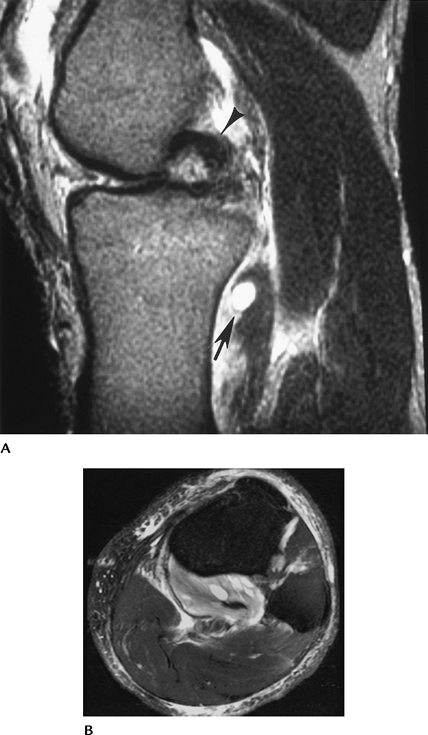

FIGURE 5-80 Popliteus muscle tear. (A) Sagittal T2-weighted image demonstrates increased signal intensity in the popliteus muscle (arrows). The PCL is hooked (arrowhead) because of an associated ACL tear. Note the joint effusion. (B)

Axial fat-suppressed fast spin-echo T2-weighted image shows abnormal signal intensity involving greater than 50% of the muscle belly (Grade 2+ strain). |